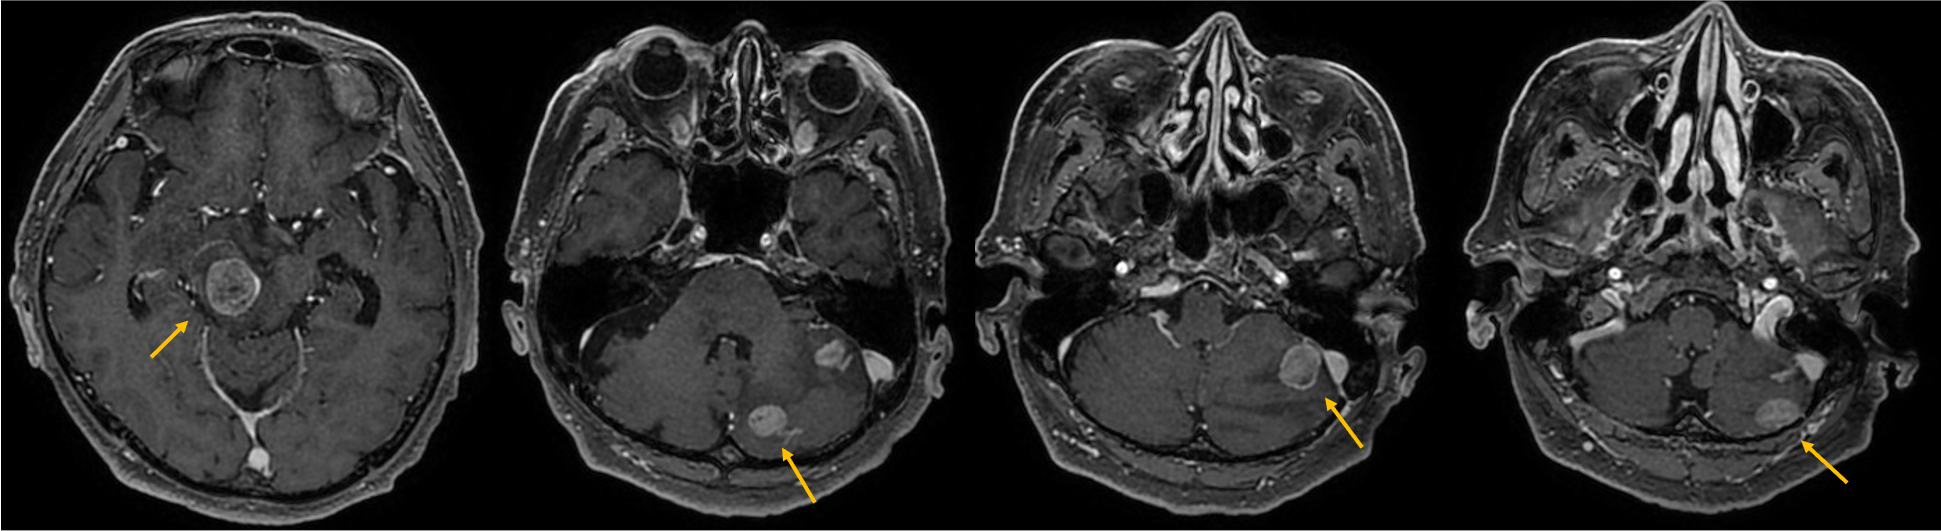

症例は70歳代男性。物が二重に見える、ふらつくとの訴えで来院。非造影MRIにて脳幹部や小脳に4個の多発脳腫瘍が認められ、症状と合致した。全身精査にて進行胃癌が発見され、その脳転移と診断された。放射線治療の適応判定のため造影MRIを施行し、新たに大脳に3個の微小転移が同定された。病変のサイズ・分布から微小転移を含む7個の腫瘍に対して定位放射線治療が可能と判断され、速やかに治療導入に至った。

本症例では先行する非造影MRIにて右中脳や左小脳の多発腫瘤が指摘され、周囲に浮腫を伴うことから転移が疑われていたが、病変数や大きさ・範囲ははっきりしなかった。造影MRIを実施することにより、右中脳に1個、左小脳に3個の2㎝大の輪郭の明瞭な腫瘍が確認されたほか、1㎝未満の3個の微小病変を新たに検出できた。非造影MRIを見直したところ7㎜の結節はFLAIRでも淡い高信号を示していたが質的診断は困難であった。3㎜の病変は非造影MRIでは存在診断不能であった。微小病変のうち2個は高位前頭葉の機能的に重要な部位に位置しており、治療適応と考えられた。造影MRIにより腫瘍の正確な個数とサイズ、分布の正確な情報を確認した後、定位放射線治療が可能と判断され、3D-FSPGR画像を治療計画に利用して迅速に治療が開始された。